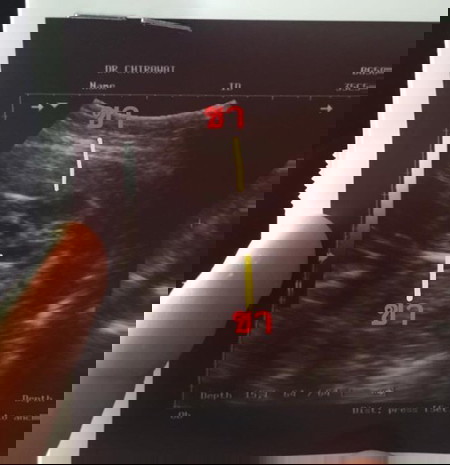

หญิงชัวร์ๆ ค่ะ สองขีดชัดมาก

หญิงค่ะ ตรงกลางผ่าเส้นแล้ว

ถ้าแบบนี้เหมือนกัน หญิงค่ะ

ผู้ญ ป่าวค่ะ ตรงกลางมีขีด

หญิงคะชัดมาก เป็นกลีบเลย

เหมือนเป็นกลีบนะแม่